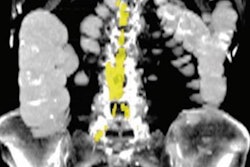

Next, the researchers utilized their previous deep-learning approach to perform fully automated analysis at the L3 vertebral level for three body composition areas: skeletal muscle area, visceral fat area, and subcutaneous fat area. Reference curves normalized by age, sex, and race were used to generate z scores for the three body composition areas. Any subsequent myocardial infarction or stroke among the participants was determined by a review of their electronic health records.